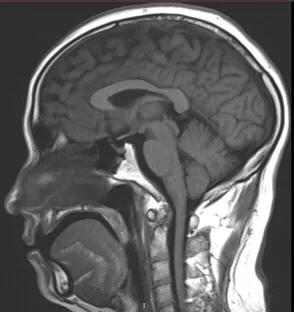

再简单说说MRI,磁共振成像。MRI要比CT复杂得多。在磁共振成像发明的初期,科学家们将它命名为核磁共振成像(NMRI),由于有一个“核”字,极容易导致人们将其与核反应、放射性核素联系到一块儿。其实是完全不同的概念,两者风马牛不相及。工作中,很多的朋友、患者问到这个问题,解释了无数遍。其实,简单的想一想,如果真有核辐射损害,怎么可以用于大众检查身体呢?这种误解,在国内外均发生过。后来,国际上统一命名,英文是Magnetic Resonance Imaging,简称MRI。这就是其名称的来源。国内呢,也把“核磁共振”改成了“磁共振”,以免误解。直到今天,依然有老一辈的人叫做“核磁共振”,其实不用担心。那么,磁共振MRI是怎样成像的呢?说起来十分复杂,需要专门学习,是物理学和计算机的科学。简单地说,将人体置于一个静磁场中,我们身体细胞的原子核就会按照静磁场的方向有顺序的排队;此时,在检查部位(比如脑部)发射电磁脉冲(波长数米),这些排好队的原子就会发生偏转,将电磁脉冲停止以后,脑部原子核就会发生共振现象,即昌盛共振信号。此时用信号接收器接受信号,并经过放大、数模转换(与CT雷同),就会得到MRI图像了。从其原理可以看出,除了磁场与脉冲以外,无任何外加因素,对人体不产生危害,孕妇、婴幼儿都可以行MRI检查的,十分安全。自上世纪80年代起,MRI已经广泛运用了40年,时间验证是最可靠的。至于静磁场的场强、电磁脉冲对人体是否有影响,作者将在以后章节阐述。

正常脑MRI图像